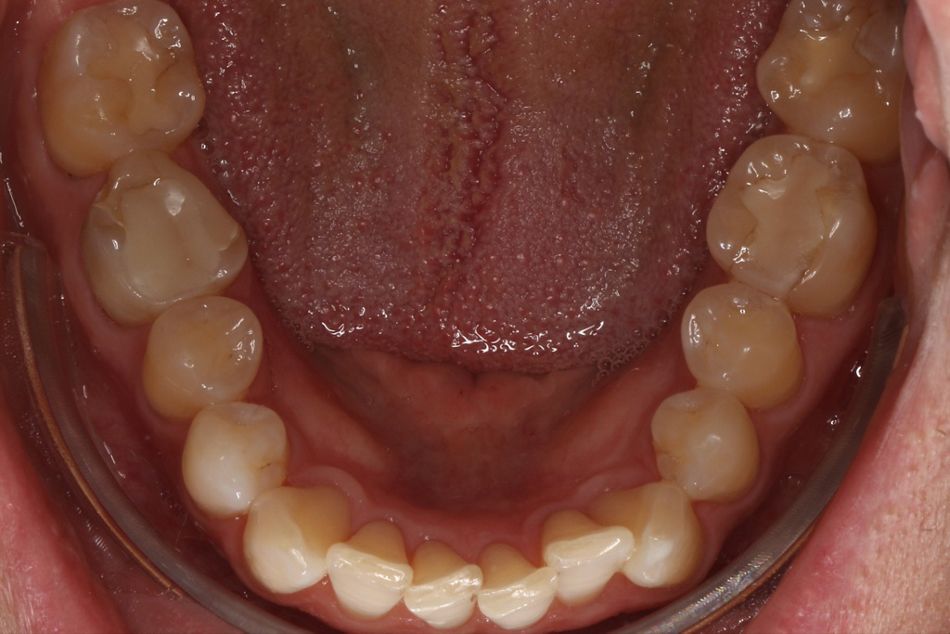

Ausgangssituation

Der Patient stellte sich mit den folgenden Symptomen vor: Er beschrieb das Gefühl, nicht genug Platz für seinen Unterkiefer in der sagittalen Ebene zu haben und hatte sich angewöhnt seine Unterkieferfront stetig gegen die Oberkieferfront zu drücken. Dies beschrieb er als “sehr unangenehm und anstrengend”. Bei Palpation war der M. masseter druckdolent, hypertroph und erhärtet. Die aktive Mundöffnung lag bei 38mm. Passiv ließ sich das auf 42mm erweitern. Es gab statische Frontzahnkontakte in zentrischer Relation. Die Inklination der Oberkiefer Incisivi war größer als 90° im Verhältnis zur Okklusionsebene. Es war schon eine deutliche Attrition im Bereich der Schneidekanten der Oberkieferfront, sowie eine Protrusion der Unterkieferincisivi aufgrund von tertiärem Engstand zu verzeichnen.

Foto Status vor Behandlung